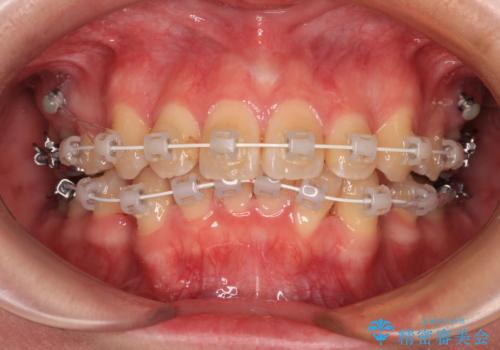

- 矯正装置

- 審美装置

- 上下前歯のデコボコを気にして来院された患者様です。

口元の突出感はあまりなかったものの、デコボコを非抜歯で改善すると出っ歯になる可能性があるため、上下左右の第一小臼歯4本を抜歯し、ワイヤー装置にて矯正治療を行うこととしました。

口元の突出感はなかったものの、捻転や八重歯を改善するために補助装置を併用する必要がありました。

予定の2年半を越えてしまいましたが、無事にきれいな口元に仕上げることができました。